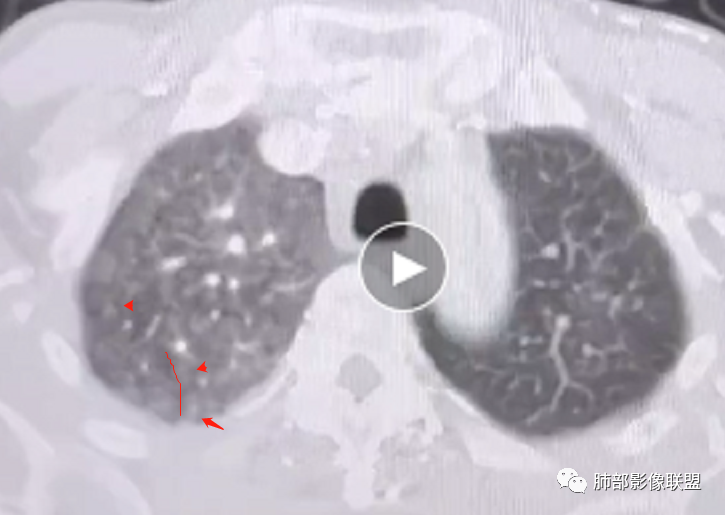

2.右肺广泛密度增高、腺泡结节样磨玻璃影,血管影明显扩张,小叶间隔增厚。

4.左肺相对广泛低密度、血管纤细(显著)。

7.肺动脉主干扩张,左侧肺动脉主干见混杂密度影,上下肺动脉似不能连续追踪。

(增强:左肺动脉充盈缺损、闭塞)

5.影像左肺动脉栓塞、闭塞——上下肺动脉以远相对纤细——左肺动脉“断供”,且存在支气管动脉扩张可能。